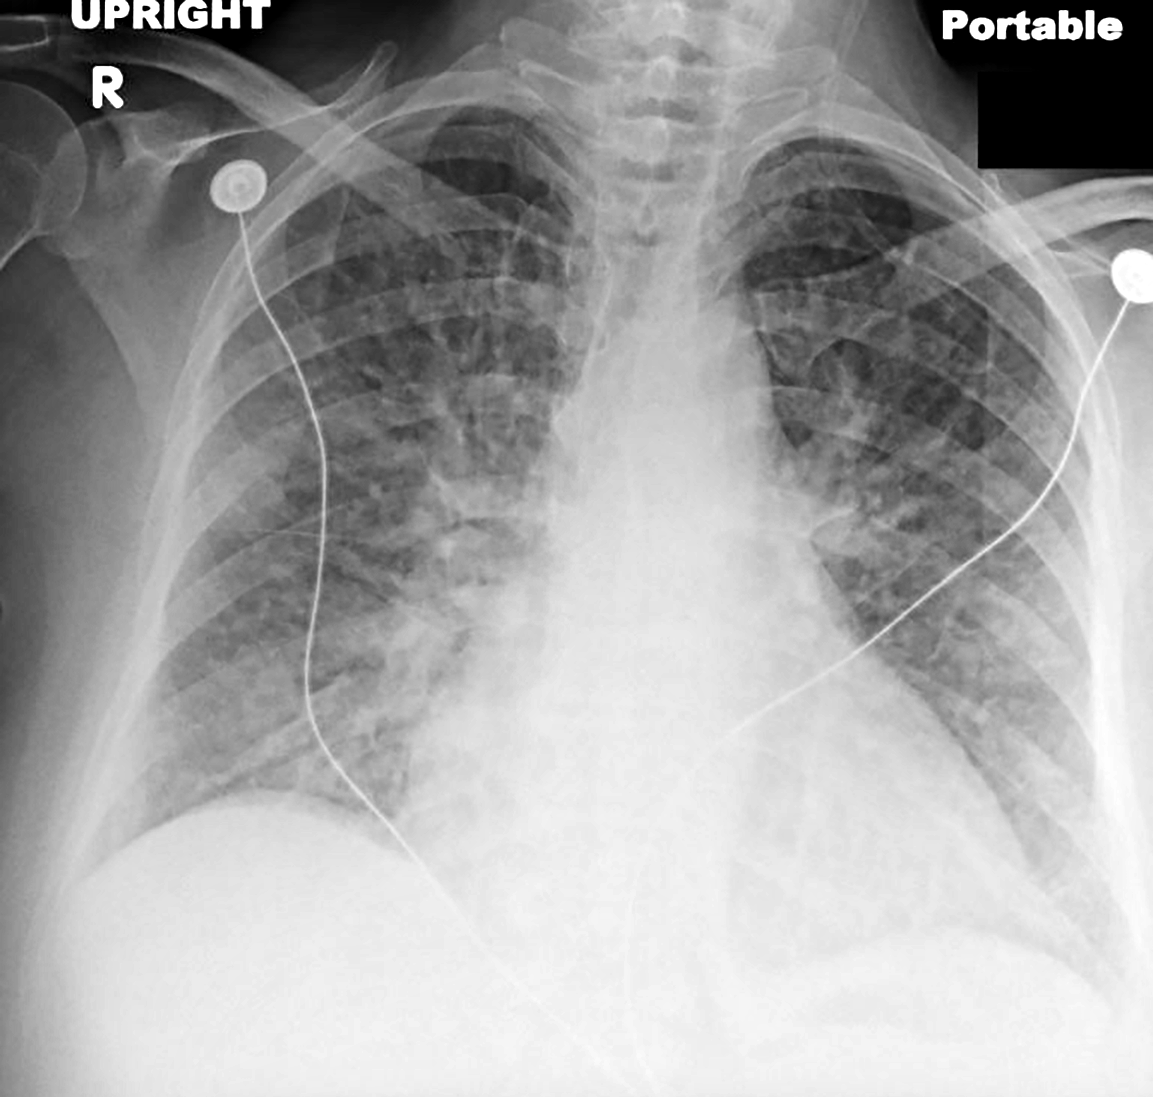

Topic 2

alternative diagnosis to consider in CHF

Further Explanation: